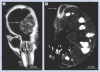

Materials & methods: Gold nanoparticles approximately 11 nm in size were injected intravenously and brains imaged using microcomputed tomography. A total of 15 h after an intravenous dose of 4 g Au/kg was administered, brains were irradiated with 30 Gy 100 kVp x-rays.

Results: Gold uptake gave a 19:1 tumor to normal brain ratio with 1.5% w/w gold in tumor, calculated to increase local radiation dose by approximately 300%. Mice receiving gold and radiation (30 Gy) demonstrated 50% long term (>1 year) tumor-free survival, whereas all mice receiving radiation only died.

Conclusion: Intravenously injected gold nanoparticles cross the blood-tumor barrier, but are largely blocked by the normal blood-brain barrier, enabling high-resolution computed tomography tumor imaging. Gold radiation enhancement significantly improved long-term survival compared with radiotherapy alone. This approach holds promise to improve therapy of human brain tumors and other cancers.